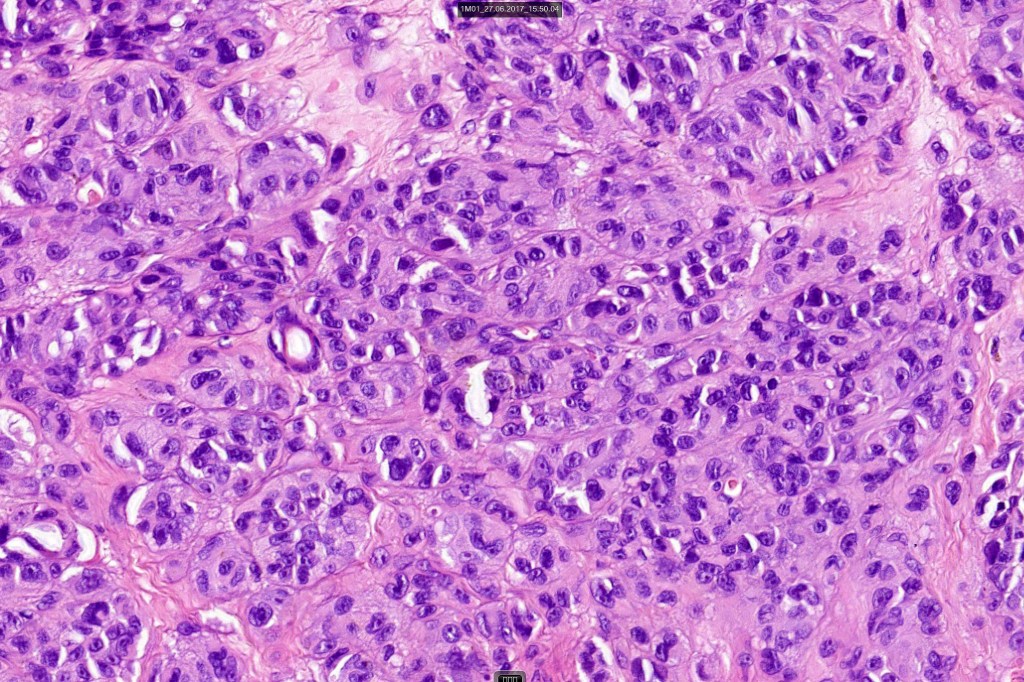

•Mimics type-A cells, (lesions which mimic type B nevus cells are often classified as small cell melanoma, this is important as the differential diagnosis is very different- see separate blog)

•Subtle or not so subtle impaired maturation with depth (sometimes this is evident at scanning magnification)

•Subtle nucleolar prominence

•Subtle pleomorphism

•Mitoses invariable including often in the deep aspect